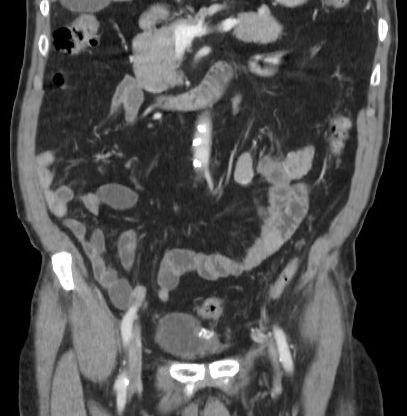

A 77-year-old patient with history of non muscle invasive and recurrent multifocal bladder tumour (pTaG2), with superficial 4-mm recurrence in the fundus bladder mucosa during the follow-up, underwent a transurethral resection of bladder tumor (TURB). Without bladder perforation suspected, intravesical instillation Mitomycin-C in the immediate postoperative period was administered. In cystoscopy, 3 months later, with the patient being asymptomatic, a fibrino-stone like growing was observed, arising from fundus bladder mucosa (1, 2). In an attempt to dismiss a post TURB leak, a biopsy of the fibrinous material was taken and URO-CT performed, which revealed irregularity and a scar tract with some calcifications within the bladder anterior wall (Fig.1 and Fig.2). The histological result of the sample taken was adipose tissue, necrosis, lymphoplasmacytic inflammatory infiltrate and dystrophic calcifications (3), compatible with encrusted cystitis. With those findings in the anatomopathological report, urine sample was analyzed. The pH of the urine was 6 and the culture was negative, so encrustated cystitis was dismissed (4). Most probable, the changes in the bladder mucosa were due to a reactive process to the intravesical instillation of Mytomicin-C in a non-suspected microscopic perforation of bladder wall. During the follow-up after biopsy, the patient was asymptomatic and without pathological findings in the cystoscopy.